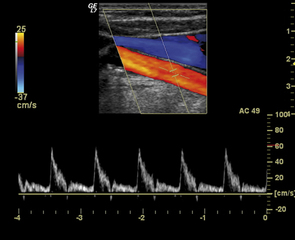

Si conclude oggi, mercoledì 14 dicembre, presso la sala convegni dell’ospedale di Trani, la seconda edizione del corso teorico-pratico di Ecolordoppler, organizzato dal dottor Francesco Nemore e dai colleghi Pollice e Scarabino è patrocinato da Sirm Puglia, Asl Bt ed Ordine dei medici e chirurghi della provincia Bat.

Con l'evento, che si rivolge a medici radiologi, provenienti da tutta Italia, che intendono approfondire le loro conoscenze sull’argomento, si esaminera... (continua ...)